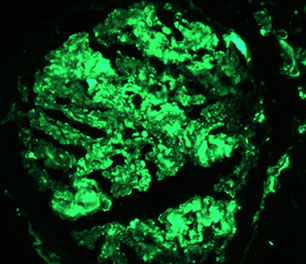

Amyloidosis

Assoc c MM, chronic conditions, TB, RA

- Multiple myeloma can cause 1) light chain deposition dz, 2) cast nephropathy, or 3) amyloidosis

- in amyloidosis the mesangium gets amyloid deposits first

- myeloma causes AL or "light chain" amyloid; chronic infx and chronic inflam assoc c AA amyloid,

- kidneys usually slightly enlarged

LM: (+) Congo-red stain and apple-green birefringence (c polarized light)

- subendothelial and mesangial amyloid deposits

- fibrillary glomerulonephritis is a type of amyloidosis that does not stain for Congo red yet has amyloid-like fibrils on EM

- can have nodular light chain glomerulopathy or cryoglobulinemic glomerulonephritis

IF: negative or can stain for LC if AL amyloid

EM: Pick-up sticks arrangement (8-12 nm [small])

Ddx: fibrillary or immunotactoid glomerulopathy (has mesangial expansion that is negative for Congo red, IgG on IHC, fibrils 10-50 nm on EM)